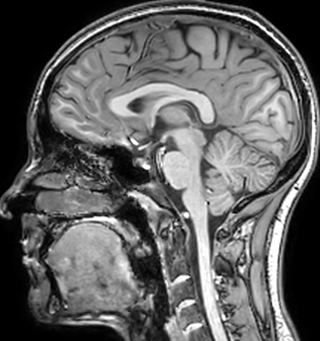

Myelin water imaging (MWI) is a breakthrough technique that was pioneered at UBC for measuring myelin content in the brain, in vivo. “Because the T2 time of water in myelin is much shorter than the T2 of water in the intraand extracellular spaces, we can separate out the myelin water signal.”

The techniques for measuring myelin have changed a lot over the years. “Since we are using the Elition, our myelin water images are much better. We're now acquiring 1 x 2 x 5 mm voxels and displaying at 1 x 1 x 2.5 mm. For a whole brain we can now measure the fraction of water in the myelin component in only about five or six minutes,” Dr. MacKay says.

of limiting MWI to the brain, even without the cerebellum, we can now spend about the same amount of time and scan the whole brain and the cervical spinal cord, which is a huge boost for us.” Dr. Rauscher says, “For MWI we perform 3D T2 with 32 or more echoes. This used to take a long time, but with Compressed SENSE we can decrease this to ten minutes for the whole head. Because of the large field of view (FOV) on the readout direction, we even get information from the brainstem, which we previously missed when we were using the GRASE approach. Having the whole head scan is nice because it has spatial resolution, orientation and FOV that are comparable to the standard 3D clinical MS scans, including the FLAIR and 3D T2, and a 3D T1 for brain volume.”

According to Dr. MacKay, MWI images benefit from Elition’s high quality gradients. “We need good gradients because we want to be able to do multi-echo sequences that have short TE times.”

Dr. Rauscher says, “With better gradients we can use a shorter echo spacing on the spin echo, so we get better sampling of the rapidly decaying myelin signal, which typically has T2 of around 10-20 milliseconds at 3 Tesla. If we can reduce echo spacing from about 8 to 5-6 milliseconds, we get a much better sampling of the short decay component and increase our SNR, which is a big advantage. The same is true for multi-echo gradient echo which we use for susceptibility mapping and for mapping venous vessels in MS.”